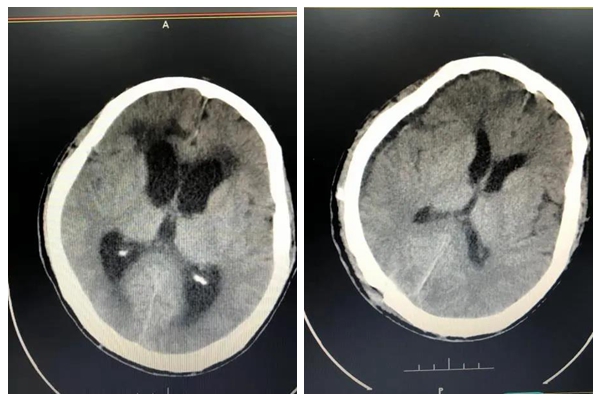

“請(qǐng)你們放心,我們一定為病人討論制定最適宜的治療方案,盡最大努力幫助他擺脫生命危險(xiǎn)?!卑鲠t(yī)一附院蕭縣醫(yī)院神經(jīng)外科第一主任婁飛云教授的一番話,讓患者家屬心中燃起新的希望。患者徐某先后前往多家三甲醫(yī)院就醫(yī),病情復(fù)雜,伴術(shù)后腦積水,肺部感染,無意識(shí),昏迷狀態(tài)。為了幫助徐先生度過危機(jī),婁飛云教授帶領(lǐng)神經(jīng)外科團(tuán)隊(duì)針對(duì)患者病情經(jīng)過詳細(xì)分析、充分討論,決定對(duì)患者實(shí)施“腦室-腹腔分流”手術(shù),用專業(yè)的技術(shù)幫助患者點(diǎn)燃康復(fù)的希望。7月23日,手術(shù)正式開始,通過特定的皮下通道將腦室內(nèi)的腦脊液引流到腹腔中,僅僅一個(gè)多小時(shí),手術(shù)順利完成。術(shù)后第三天患者神志已轉(zhuǎn)清楚,雙手活動(dòng)自如,精神狀況較好,患者家屬非常滿意。

“真得要感謝蚌醫(yī)一附院的專家,手術(shù)效果非常好,手術(shù)后老徐的兩個(gè)手都可以抬起來,精神也非常好,還可以給親戚朋友們揮手再見。”8月2日,婁飛云教授例行查房,在得知復(fù)查腦部CT后如果沒問題就可以出院,徐先生的愛人不停的對(duì)專家們表示感謝。